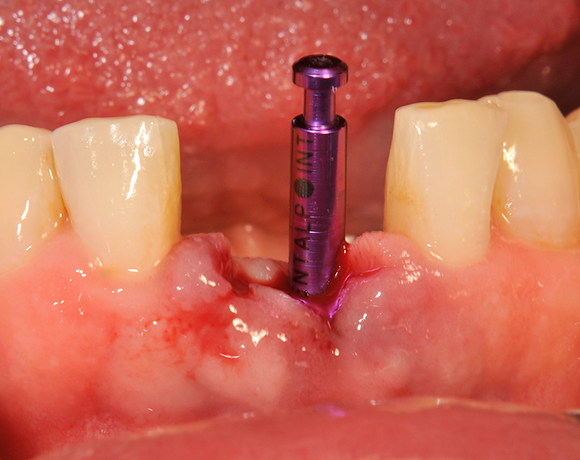

Die Keramikimplantate der Fa. Dentalpoint lassen sich auch zur Sofortimplantation verwenden. Das bedeutet, dass nach Extraktion nicht beherdeter Zähne direkt die Implantate gesetzt werden können.

Im vorliegenden Patientenfall wurden die beiden nicht erhaltungswürdigen, mittleren Unterkieferschneidezähne durch zwei Vollkeramikimlpantate ersetzt.